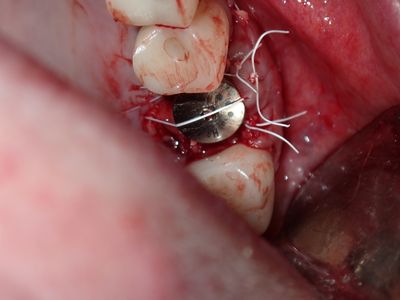

atraumatic exo 26, no loss of labial or palatal plate. Softer bone, implant osteotomy underprepared, difficult/impossible to stretch palatal flap, about 1.5mm exposued at palate, fibrin mmebrance placed on crest, socket grafted with sticky bone from 90/10 mix of mineralized cortical/xenograft